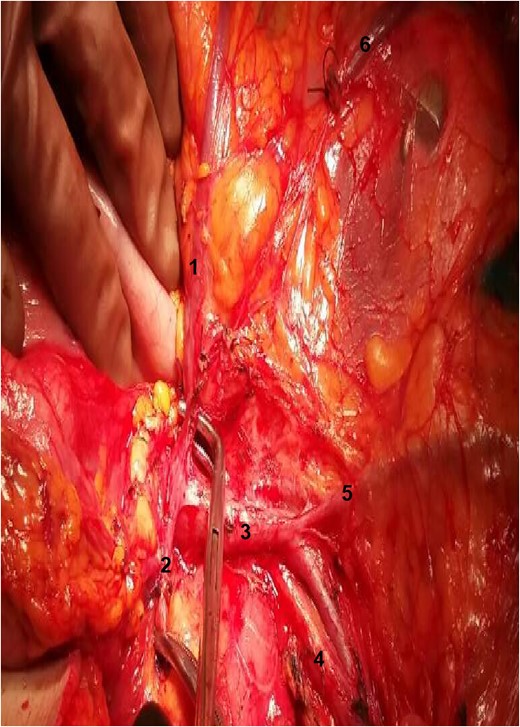

Exposure of the operative field. 1: RCA; 2: gastroepiploic artery; 3: superior mesenteric vein; 4: SMA; 5: ileocolic vein; 6: stump of right colic vein.

During the operation, surgeons attained to isolate the main supplying arteries of the right colon and their origins. The ileocolic and the middle colic arteries were observed, as typically, emerging as isolated vessels from the superior mesenteric artery (SMA). However, the origin of the RCA was nor observed from the SMA, nor from the previous arterial branches, as in common. Surgeons continued ascending dissection in order to detect the origin of the RCA that was finally observed arising from the right gastroepiploic artery (Figs 1–2). Pericolic lymph nodes and the lymph nodes that followed the central wards of the ileocolic, the middle colic and the aberrant RCA were gently dissected. The operation continued in the usual pattern. A drainage was placed and was finally removed the 6th postoperative day. The patient was discharged the 10th postoperative day with instructions. At the follow-up, the 14th postoperative day, the patient suffered no complications whatsoever.